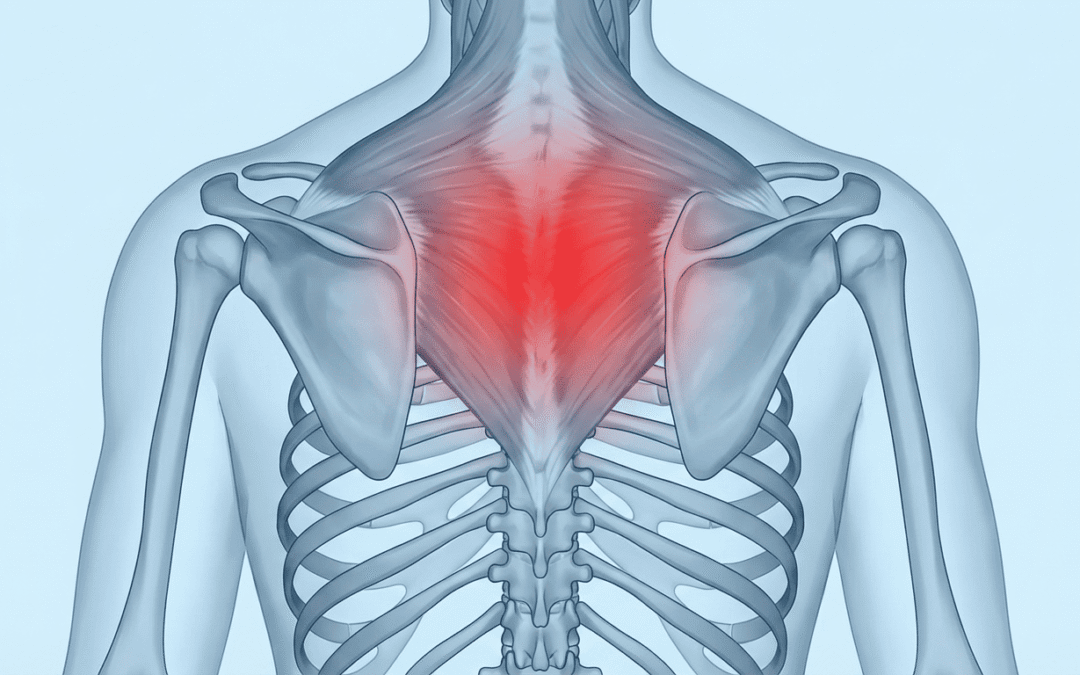

Пекучий біль між лопатками: що робити?

Пекучий біль між лопатками – це проблема, з якою багато людей стикаються щодня. Чи відчували коли-небудь цей дискомфорт? Здається, наче хтось розпалив вогонь просто під шкірою. Неприємно та нав’язливо. Іноді цей біль з’являється через травму, іноді внаслідок тривалих годинних сидінь за комп’ютером.

Що ж, панове, спричиняє цей пекучий біль?

- Погана постава: Якщо ви працюєте за комп’ютером, схилившись над столом, приділяйте увагу своїй поставі. Пам’ятайте про це.

- Травми спини: Може на перший погляд здаватися, що це незначна жартівлива травма, але її наслідки можуть бути серйозними. Будьте обережні.

- Міжхребцеві грижі: Здається, грізна проблема, чи не так? Це питання медицини, яке потребує професійної діагностики.

- М’язове перенапруження: Чи то спорт, чи то робота на дачі – м’язи не завжди витримують.